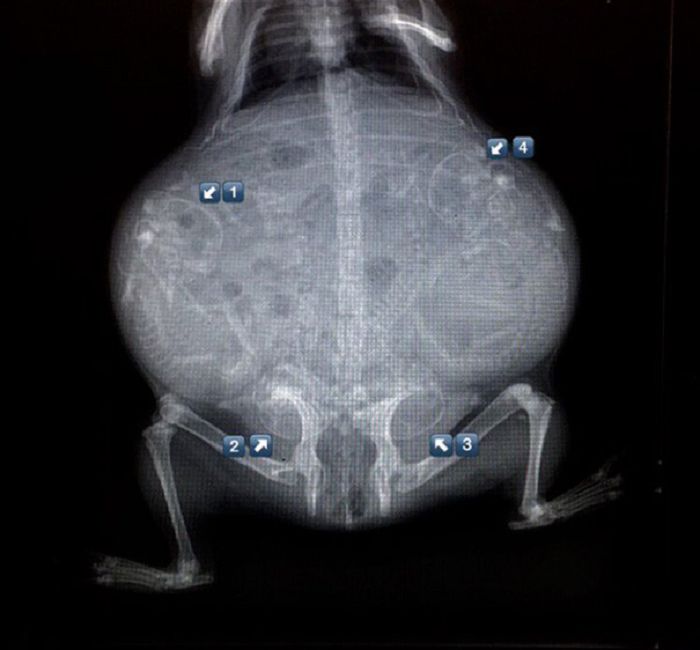

以下就是一些动物在怀孕时的X光片。

7. 豚鼠